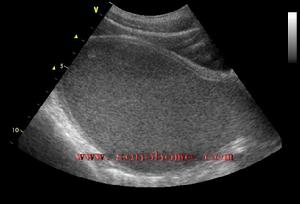

處女膜閉鎖絕大多數處女膜閉鎖患者臨床上表現為青春期後出現逐漸加劇的周期性下腹痛,但無月經來潮。嚴重者伴有便秘、肛門墜脹、尿頻或尿瀦留等症狀。檢查時見處女膜向外膨隆,表面呈紫藍色,無陰道開口。當用示指放人肛門內,可捫到陰道內有球狀包塊向直腸前壁突出。行直腸一腹部診時可在下腹部捫及位於陰道包塊上方的另一較小包塊(為經血瀦留的子宮),壓痛明顯。如用手往下按壓此包塊時,可見處女膜向外膨隆更明顯。盆腔B型超聲檢查可發現子宮及陰道內有積液。確診後應立即手術治療。先用粗針穿刺處女膜正中膨隆部,抽出褐色積血證實診斷後,即將處女膜作;形切開,引流積血。積血大部排出後,常規檢查宮頸是否正常,但不宜進一步探查宮腔以免引起上行性感染。吸盡積血後,切除多餘的處女膜,使切口呈圓形,再用3―0可吸收縫線縫合切口邊緣黏膜,以保持引流通暢和防止創緣粘連。術後留置導尿管1-2日,外陰部置消毒會陰墊,每日擦洗外陰1―2次直至積血排淨為止。術後給予抗感染藥物。

輔助檢查:C 盆腔的CT檢查 B 腹腔鏡 A 婦產科的超聲檢查 A 尿常規檢查 A 血液常規檢查